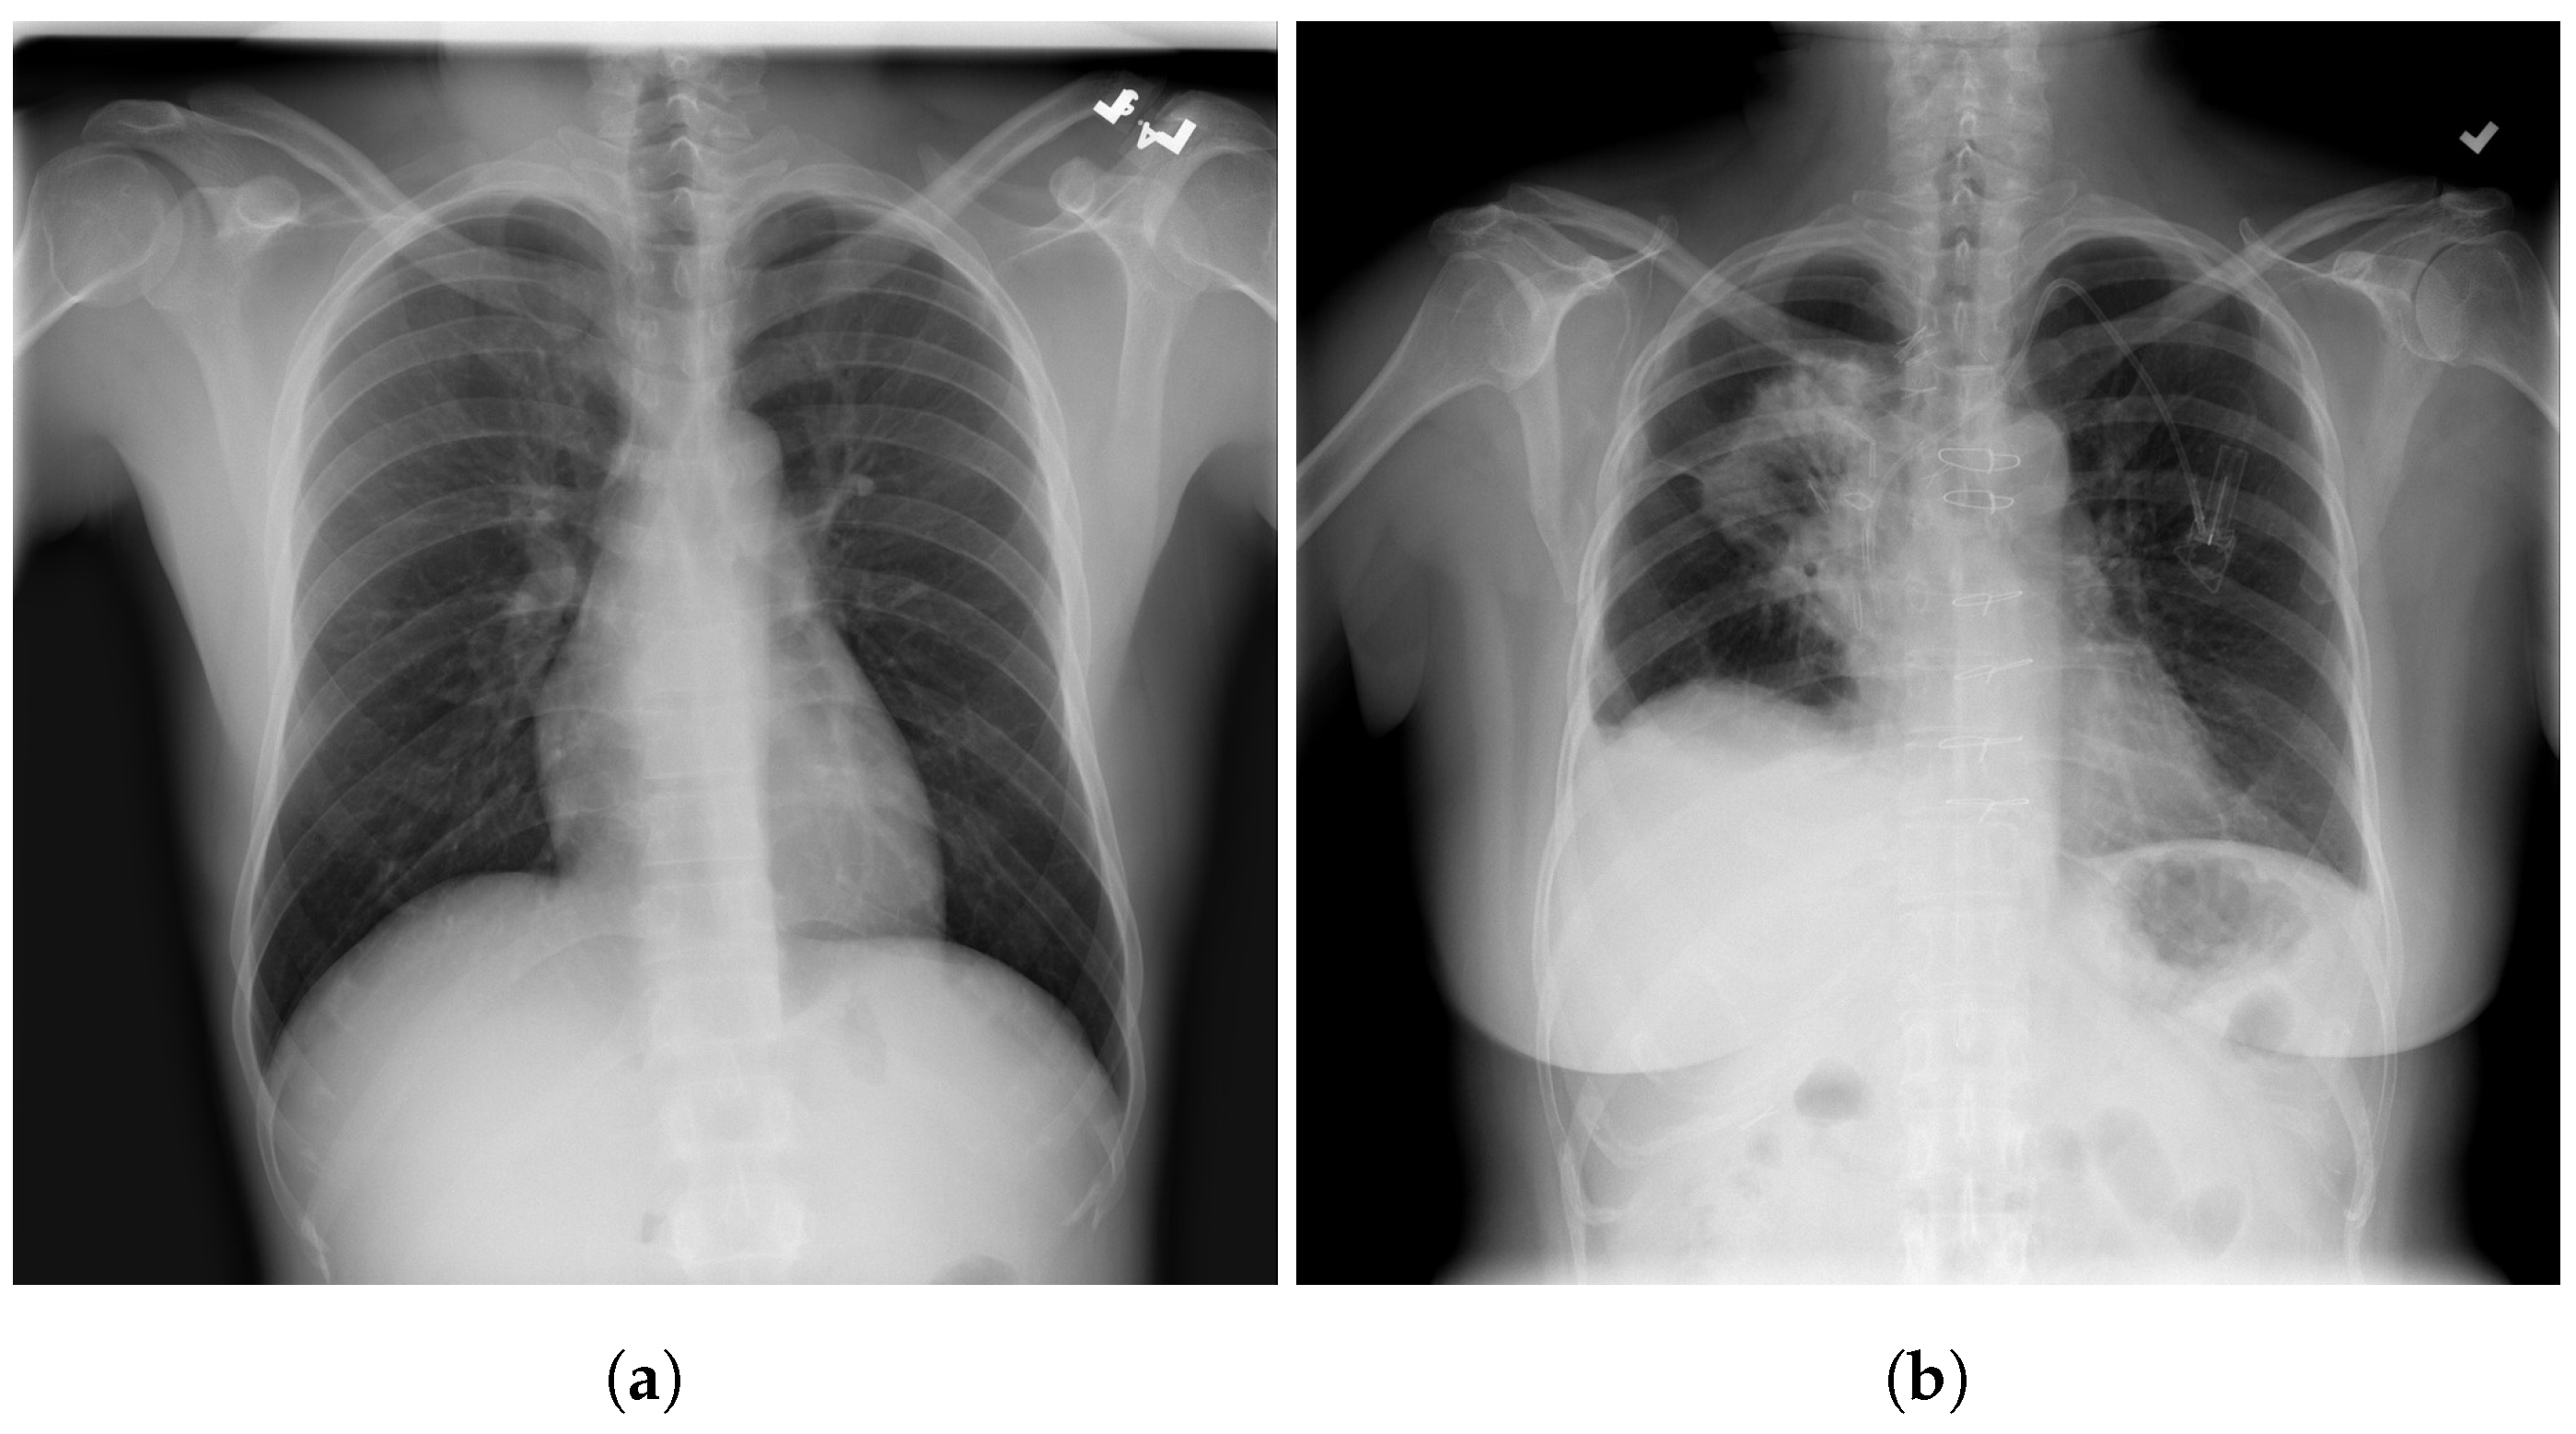

4.1. Data Distribution for Multi-Class and Binary Models

5.1. DeepCCXR-Bin for Individual Datasets

5.2. DeepCCXR-Multi for Individual Datasets